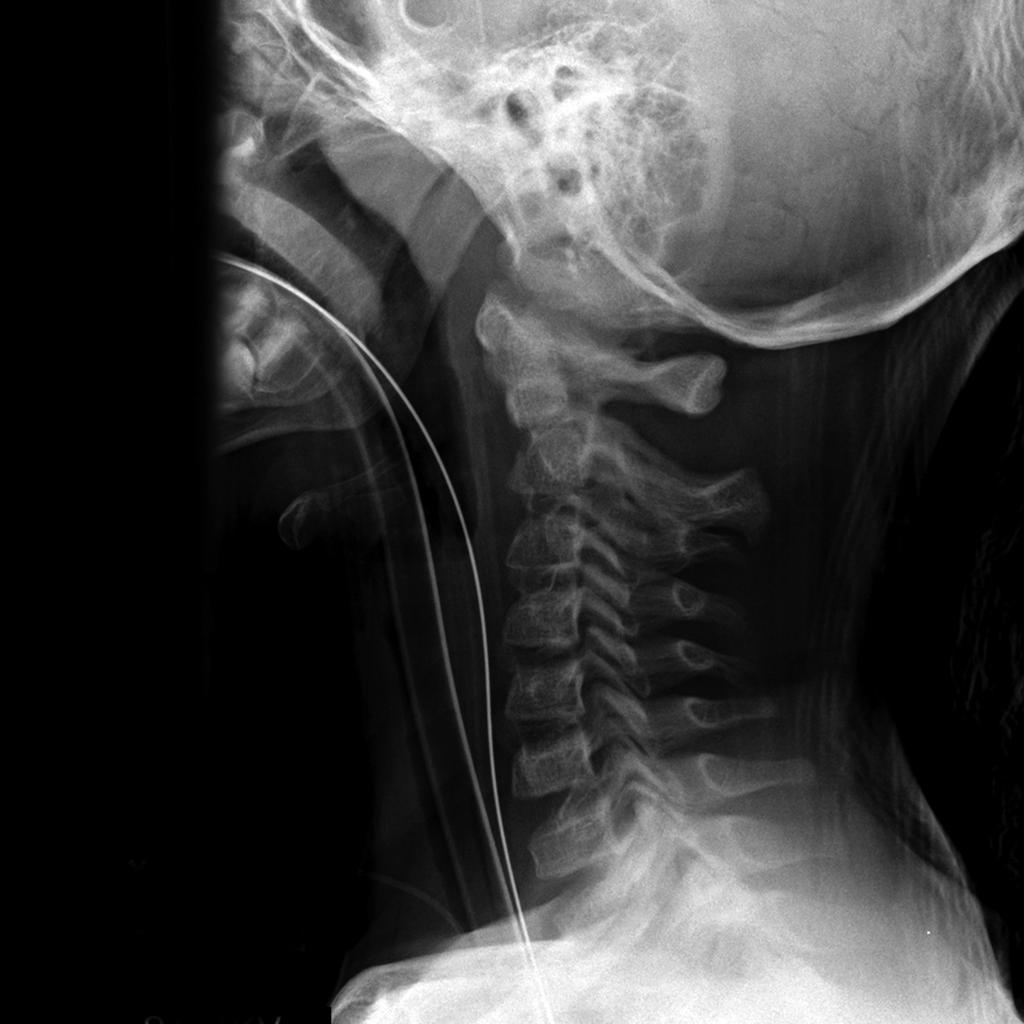

C-spine Radiographs

• By 8 to 9 years of age, cervical spine reaches adult proportions

• Cervical spine injuries in children usually occur high - from the occiput to C3 vertebra

• Fulcrum of motion in children is at the C2-C3 level rather than at the C5-C6 level in adults

• Owing to hypermobility of the c-spine because of ligamentous laxity, shallow and angled facet joints, anteriorly wedged vertebrae, and underdeveloped spinous processes

• Weak neck muscles, underdeveloped odontoid process, and large head also contribute to instability of the c-spine

• For screening, obtain lateral, AP, and odontoid views of the cervical spine

Approach

• Every lateral c-spine view should visualize at least the top of T1, of not, may need swimmer’s

• Lateral

• Upper C-spine

• Atlantodens interval (< 5 mm)

• Spinolaminar line should intersect with opisthion

• Relationship between basion and odontoid and posterior vertebral line for atlantooccipital dislocation - should be less than 12 mm (?), head usually dislocated anterior on cervical spine

• Look at odontoid

• C2 on C3 subluxation, C2 pedicles

• Lower C-spine

• Anterior vertebral body line

• Posterior vertebral body line

• Articular pillars

• Spinolaminar line

• Disc spaces should be roughly equal

• Interspinous spaces should be uniform

• Kyphotic deformity

• Prevertebral tissues (see below)